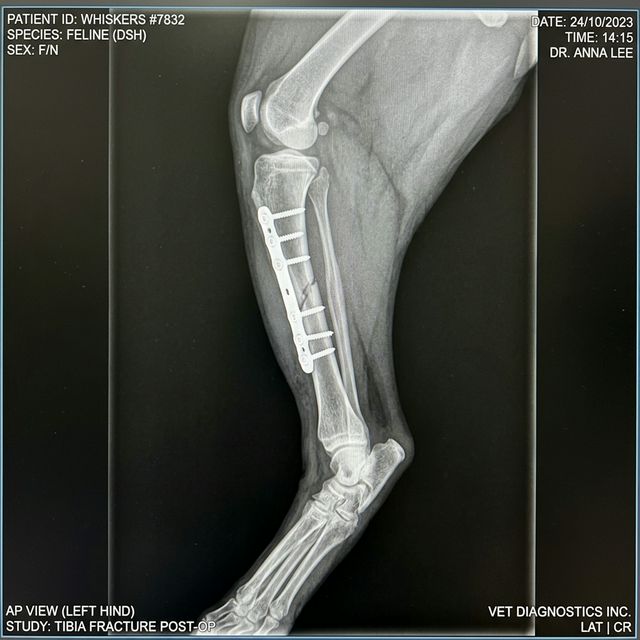

- X線検査(レントゲン)──骨折の位置・形態・粉砕の程度を評価します。複数方向から撮影します

| 外科的固定(プレート+スクリュー) | 大腿骨・橈尺骨などの長管骨骨折に多用。金属板と螺子で骨片を固定する最も確実な方法 | 100,000〜250,000円 |

手術後は術後感染・インプラント(金属固定器具)のゆるみ・骨癒合不全などの合併症リスクがあります。定期的なX線検査による経過観察が必要で、骨癒合が確認されるまで通常4〜12週間かかります。